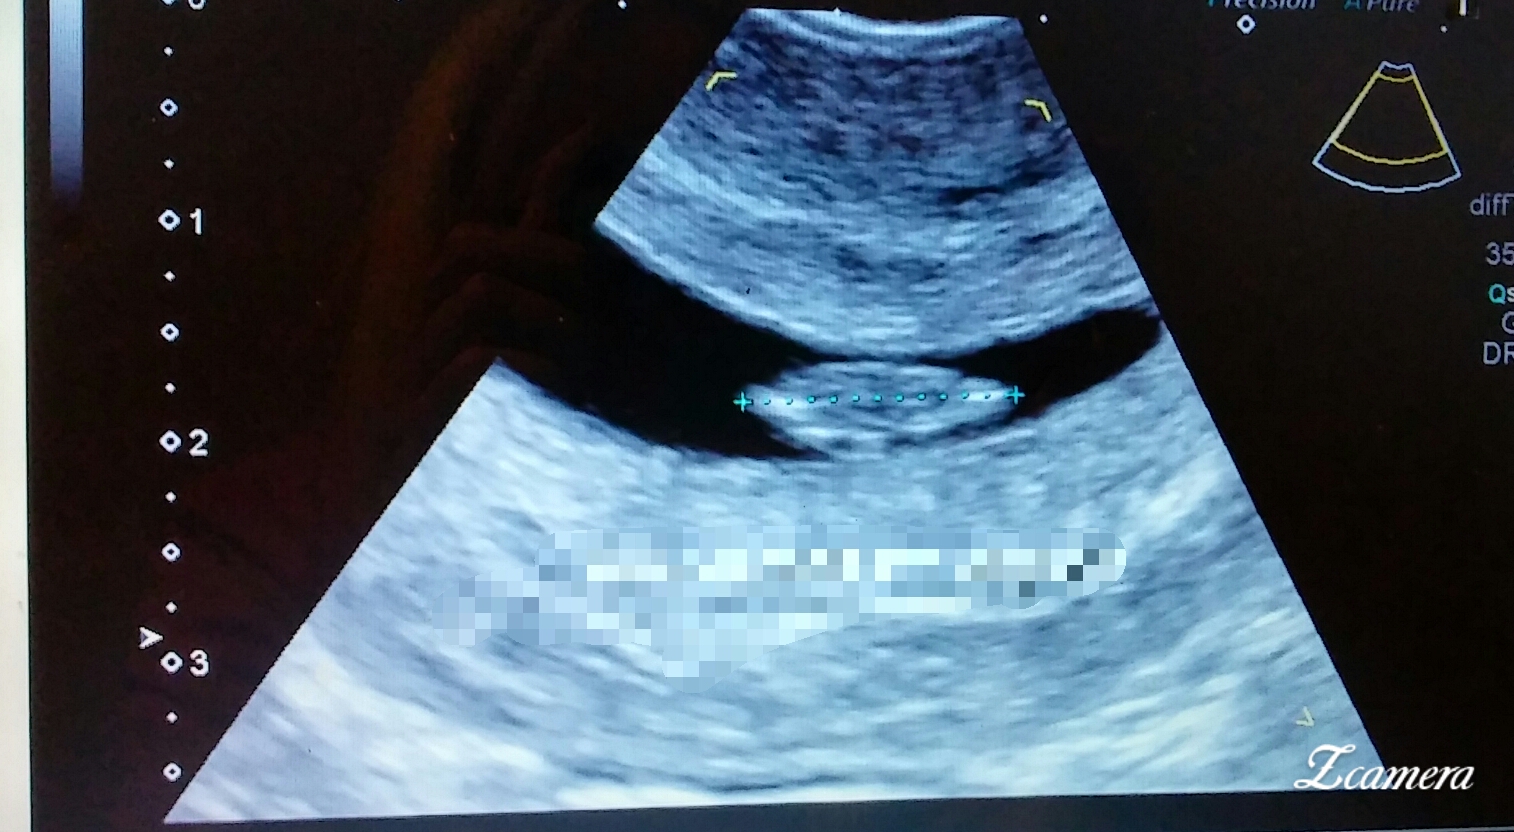

Ramzi anyone?))

Can anyone check out my ultrasound? 7weeks 3days transvaginal. Tia!